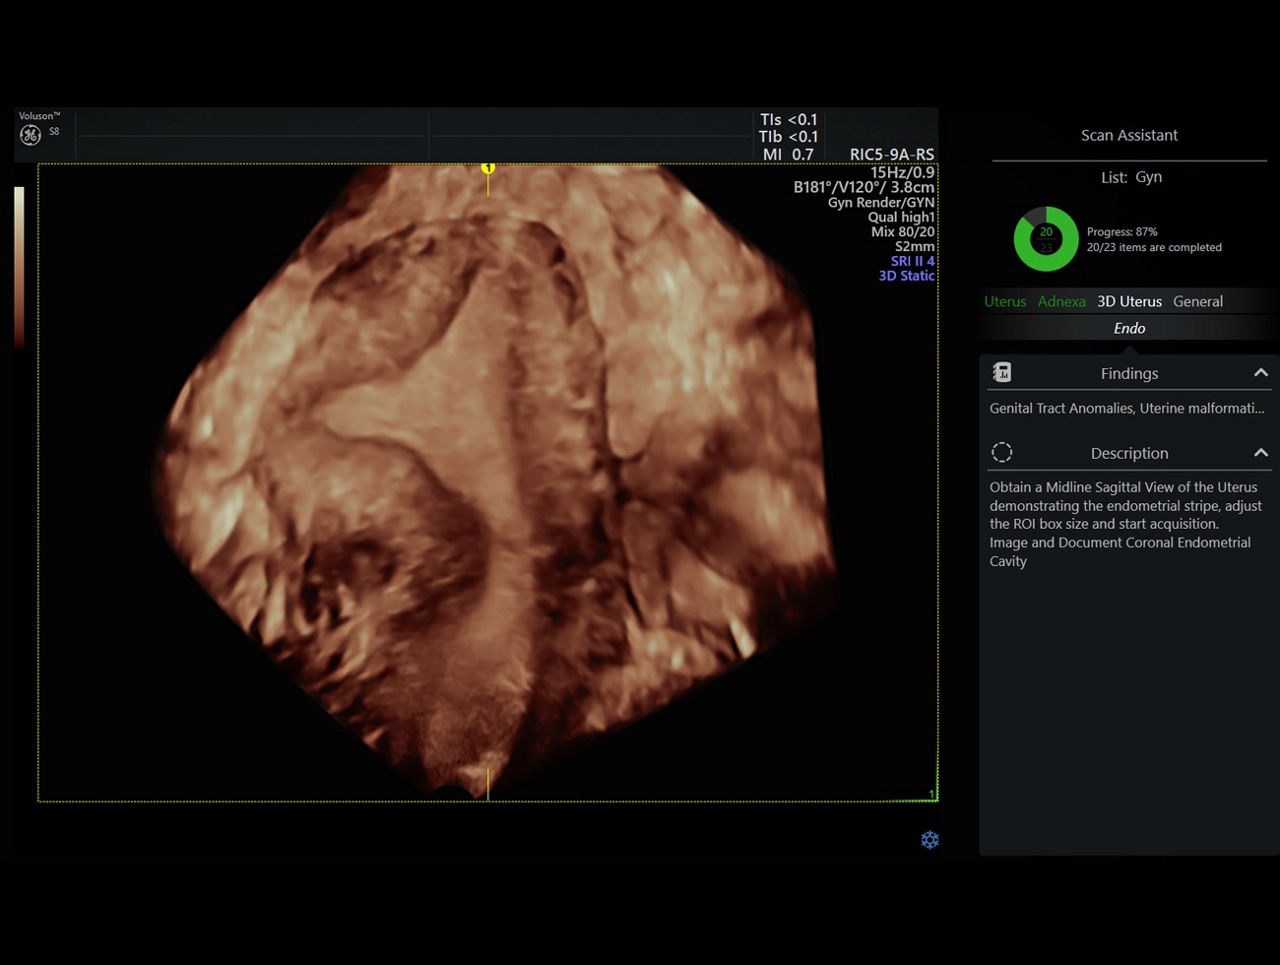

Scan Assistant

This flexible, customizable exam protocol helps reduce time required to conduct and document results by guiding you through an exam more efficiently, aiding in annotation, measurement, and reporting.